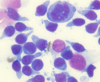

what is shown here

neutrophilic inflammation

bacteria seen